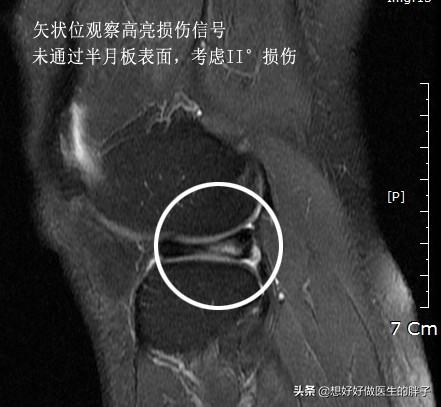

而前角内见线性高信号影就说明为I-II°半月板损伤,因为损伤信号没有到达关节面,损伤是在半月板内部的,镜下很可能看见的是正常的半月板,下面是半月板II°损伤的核磁和镜下所见,和III°损伤有天壤之别。